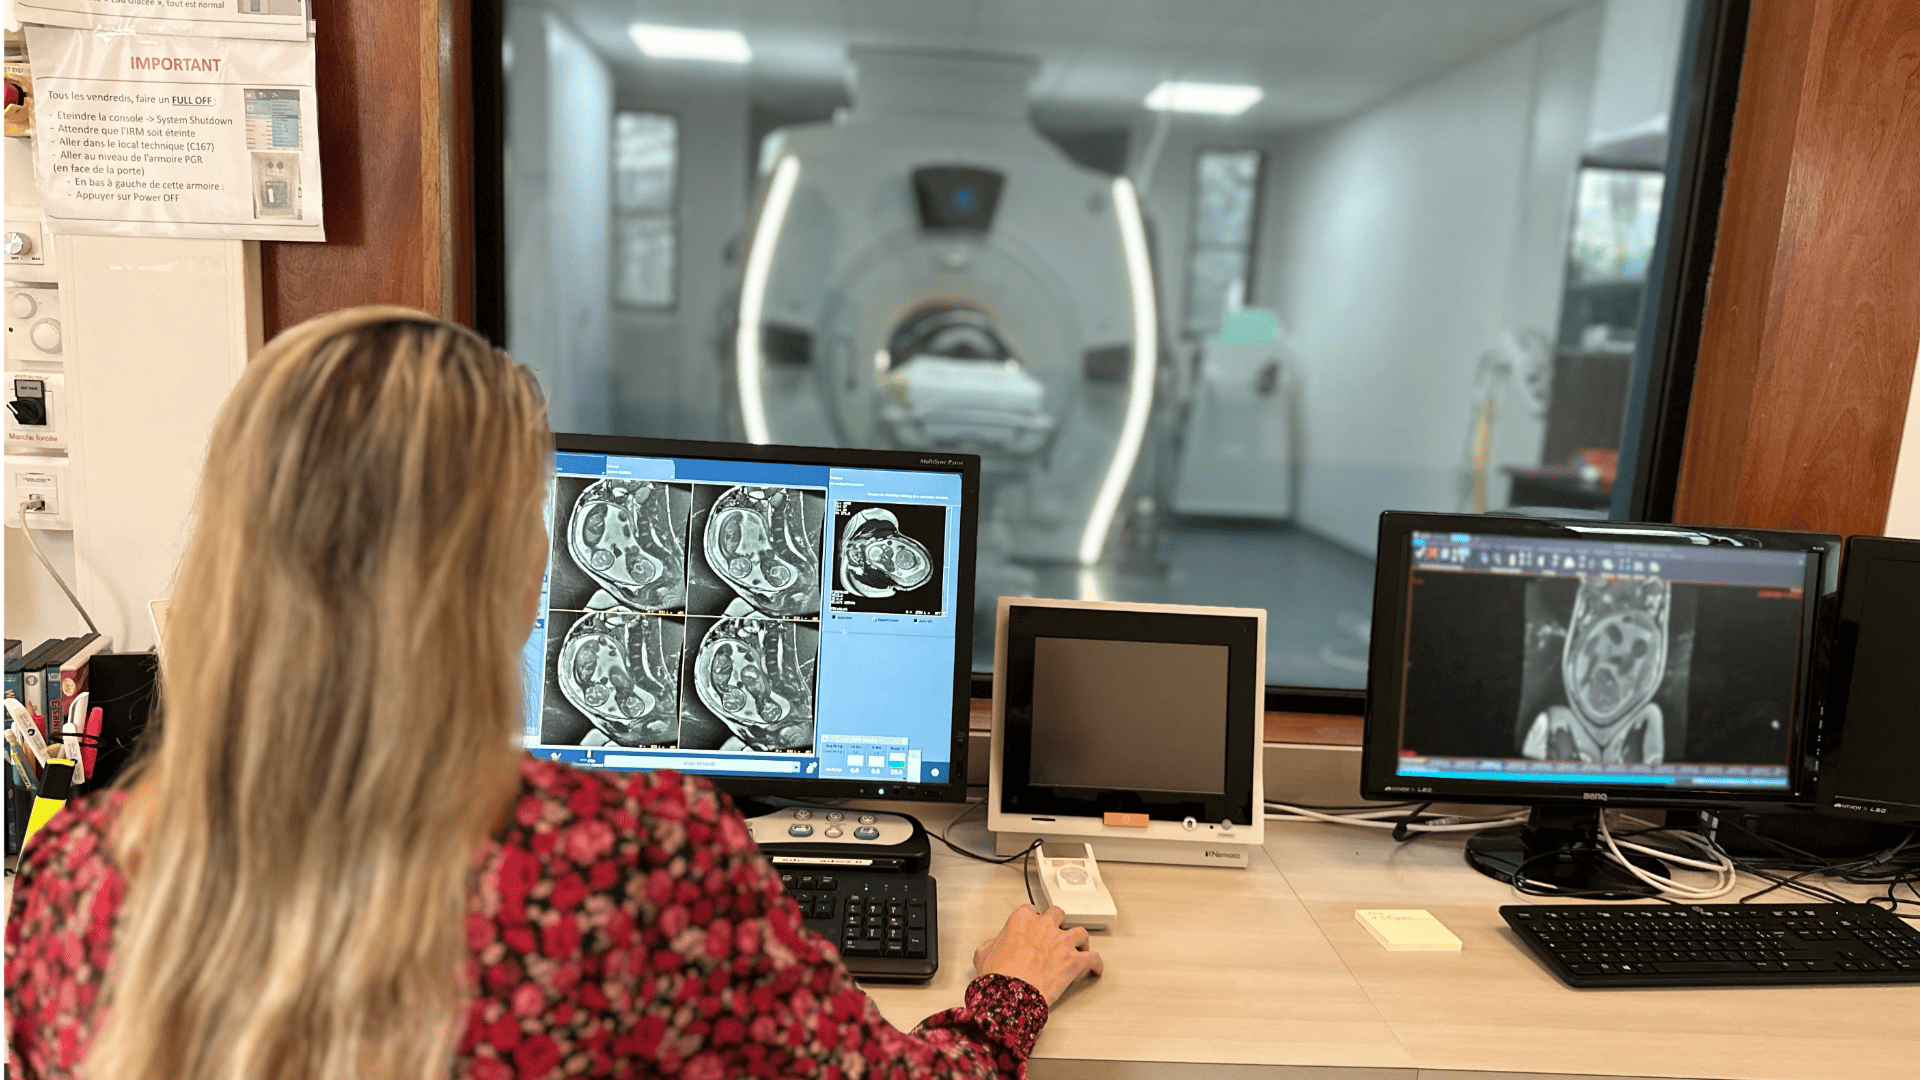

L’Université Paris Cité franchit une nouvelle étape dans le domaine de l’imagerie médicale anténatale avec l’acquisition d’un système d’Imagerie par Résonance Magnétique (IRM) 1,5T ARTIST™ de GE HealthCare. Cet équipement de pointe renforce les capacités de la Plateforme LUMIERE à l’hôpital Necker-Enfants malades, plateforme intégrée de soins, de recherche clinique et d’enseignement en imagerie médicale de la femme enceinte, du fœtus et du placenta.

L’acquisition de cette nouvelle IRM s’inscrit dans le cadre du protocole de recherche « LUMIERE SUR LE FETUS », dont les objectifs sont d’améliorer la prise en charge des pathologies anténatales, d’affiner leur pronostic et de contribuer à la réduction de la morbidité et de la mortalité à court, moyen et long terme. Cette acquisition a été rendue possible grâce au don exceptionnel de la Fondation LUMIERE d’un montant de 250k euros ainsi qu’au soutien de l’Université Paris Cité à hauteur de 670k euros.

Depuis 2020, la Plateforme LUMIERE offre aux femmes enceintes volontaires, entre 16 et 36 semaines d’aménorrhée et suivies à l’hôpital Necker-Enfants malades, la possibilité de participer activement à l’avancée de la recherche en médecine fœtale, tout en bénéficiant d’une IRM fœtale au cours de leur grossesse, réalisée dans un cadre sécurisé et encadré.

L’inclusion de ces patientes, depuis leur accueil jusqu’à la réalisation des examens d’imagerie, puis l’analyse des images et l’interprétation des résultats par des équipes expertes, enrichit une base de données structurée, unique au monde, au service de la recherche et de l’innovation en imagerie anténatale et en médecine fœtale.

Avec l’intégration de ce nouvel équipement IRM de dernière génération au sein de la Plateforme LUMIERE, l’Université Paris Cité réaffirme son engagement en faveur d’une recherche d’excellence, au service de l’innovation médicale, de la formation et de l’amélioration de la santé maternelle et néonatale.